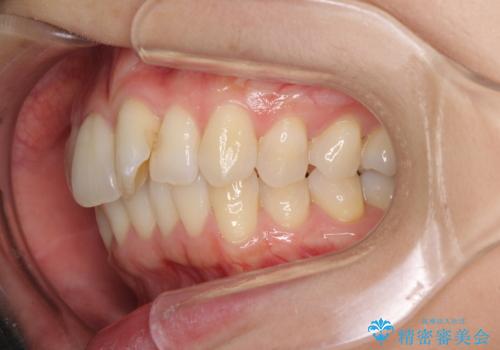

- 前歯の捻れと、それに伴う口元の突出感を気にして来院された患者様です。

上顎前歯の叢生が解消されると出っ歯になることが分かっていたので、両側奥歯付近にアンカースクリューを入れ、出っ歯を改善するためのゴムかけを行いました。

ゴムかけを頑張っていただいたので、当初の予定通り、1年強で治療を終えることができました。